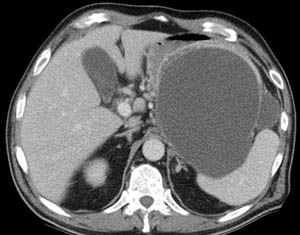

以下是引用hhcckk在2007-8-3 20:12:00的发言:[br][br]左肾周筋膜增厚,有胰腺炎的表现,胆管内高密度,结石?钙化?图片不全,遗憾[br][br]